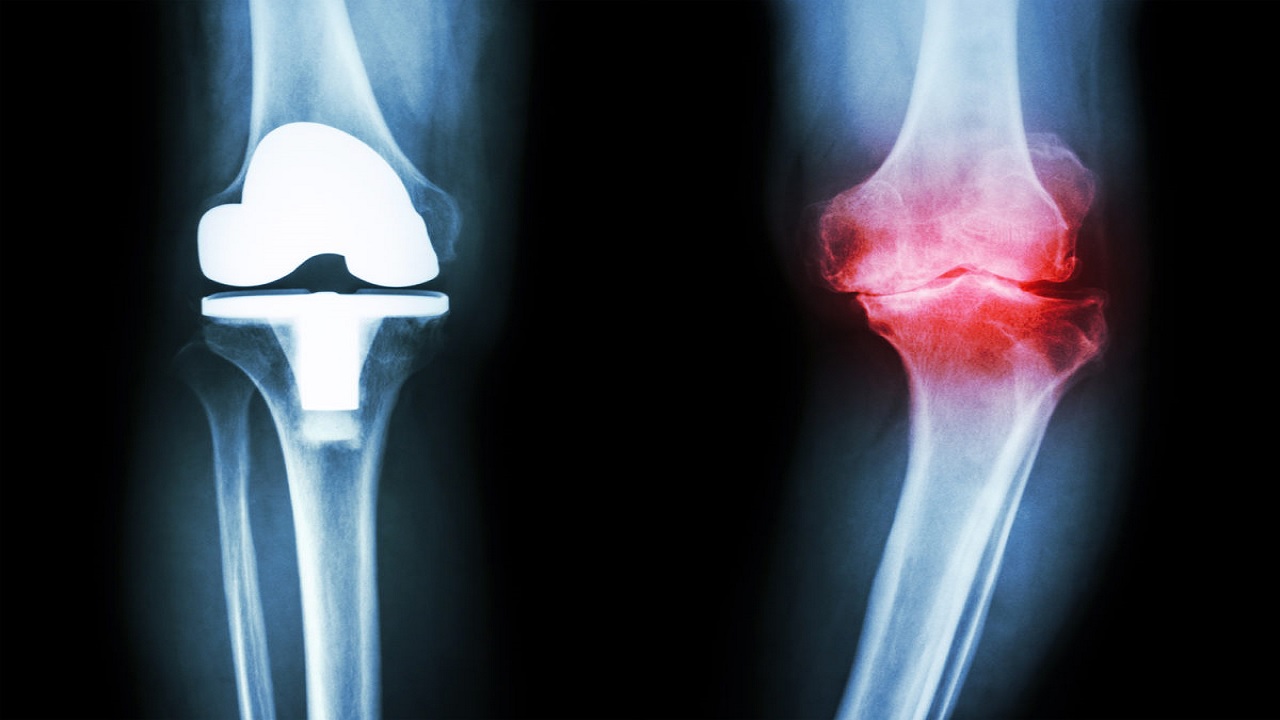

3. Эндопротезирование голеностопного сустава (эндопротез) — полная замена голеностопного сустава на искусственный.

Это сложная, высокотехнологичная операция, при успехе которой человек забывает о проблемах с голеностопным суставом на многие годы. В ходе операции хирург полностью удаляет суставные поверхности таранной и большеберцовой кости, и заменяет их металлическими имплантами, покрытыми полимерным материалом. Полимерный материал имеет низкий коэффициент трения и обеспечивает скольжение суставных поверхностей. Объём движений в суставе полный.

Полная замена голеностопного сустава: В ходе этой процедуры поврежденные хрящи и кости удаляются и заменяются новыми металлическими или пластиковыми суставными поверхностями для восстановления функции сустава.

По словам доктора Билала, эта процедура помогает сохранить подвижность суставов. Идеальные кандидаты имеют хорошее качество костей и нормальные сухожилия и связки. «Пациенты с ранее существовавшим артритом в более мелких суставах стопы, бедра или колена, которые могут ухудшиться из-за потери подвижности в голеностопном суставе, могут быть лучшими кандидатами на замену голеностопного сустава», — говорит доктор Маганти.

Однако эта операция вызывает споры и дает неоднозначные результаты. «Замена сустава сопряжена с определенными рисками, в том числе с отказом имплантата», — говорит доктор.Билал. «И это не идеальная процедура для людей, у которых есть деформации или предшествующие инфекции, приводящие к повреждению суставов».

По словам доктора Бхатт, голеностопный сустав подвергается большой нагрузке, а имплантаты не так хороши, как натуральная кость. Это сохраняет движение в голеностопном суставе, но вы должны некоторое время не стоять на ноге. «Результаты замены несущего вес сустава с плохой опорой, такого как голеностопный сустав, требуют большого хирургического опыта», — говорит доктор Маганти.

- Операция по замене сустава : Этот вид операции включает замену голеностопного сустава искусственными имплантатами и используется только в редких случаях.